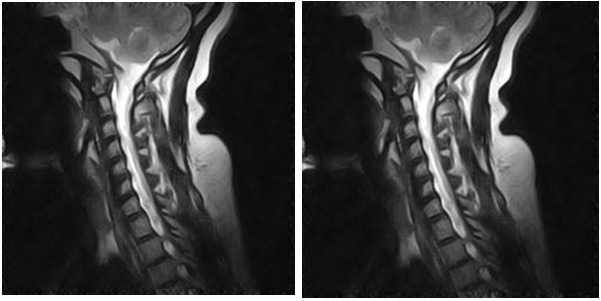

Figure 1: Spinal MRI of Case 1: Hyper-intensity at the Cervico-medullary Junction Extending More Than Three Segments.

figure 1